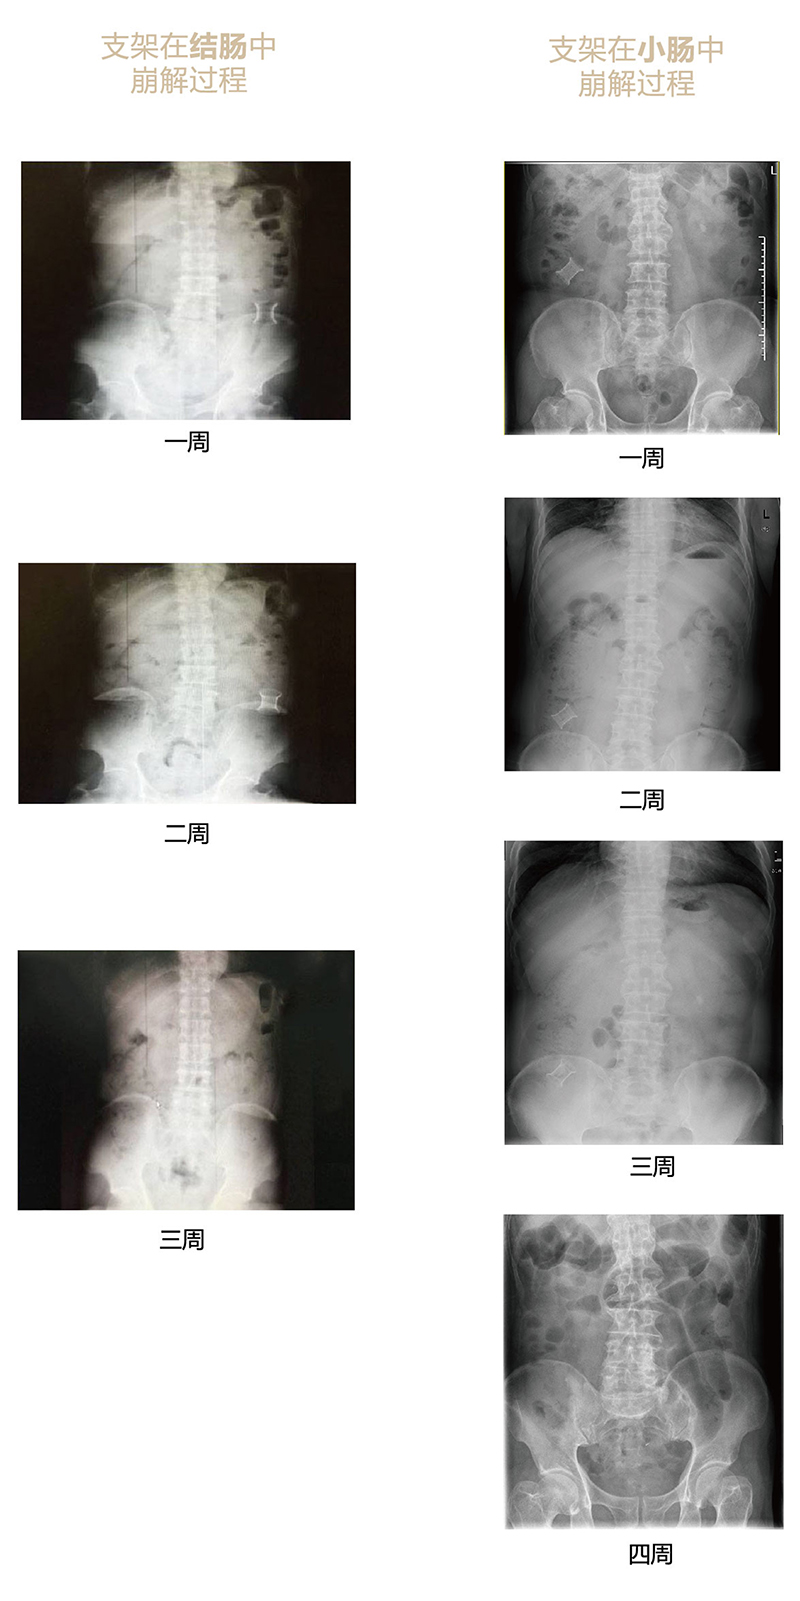

“可崩解腸道吻合器”由聚乙醇酸(PGA)與硫酸鋇按重量比7:1混合注塑制成,在X線下顯影,可動(dòng)態(tài)追蹤可崩解腸道吻合器(支架)在腸道內(nèi)崩解過程。

為解決該問題,蔡秀軍教授在“支架法空腔臟器吻合技術(shù)”的理念基礎(chǔ)上,又發(fā)明了“蔡氏腸轉(zhuǎn)流術(shù)”,這是一種應(yīng)用“可崩解腸道吻合器HB型(可崩解腸轉(zhuǎn)流支架)”(發(fā)明專利號(hào):201910794214.3),的支架法腸道轉(zhuǎn)流術(shù),此創(chuàng)新術(shù)式既能保護(hù)低位吻合口,更避免了回納術(shù)??杀澜饽c轉(zhuǎn)流支架在直腸癌根治術(shù)中植入遠(yuǎn)端回腸,可確保完全阻斷腸腔,用腸造瘺管在轉(zhuǎn)流支架近端行腸造瘺,起到完全轉(zhuǎn)流的作用。腸轉(zhuǎn)流支架在二至三周內(nèi)逐漸崩解,并在四周內(nèi)完全排出體外,恢復(fù)腸道通暢后拔除造瘺管,避免了傳統(tǒng)造口回納的二次手術(shù)。該創(chuàng)新術(shù)式具有方法簡(jiǎn)單、吻合時(shí)間短、人體內(nèi)無異物永久殘留、不破壞吻合口粘膜下血管,并能預(yù)防吻合口漏、可避免人工肛門留置及二次手術(shù)、治療周期可縮短至二至四周、患者生理心理創(chuàng)傷顯著減少。